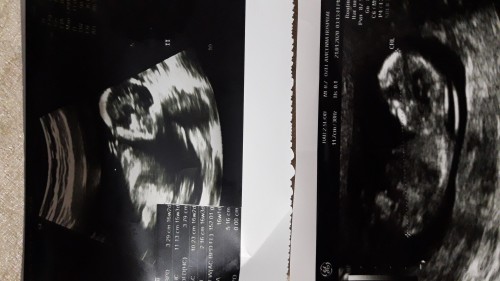

16 haftalık  olduk ancak halaaa bebeğim  kendini göstermiyor  :) üstteki  bugün  den digeri ocak ayından  olan ultrason resmi